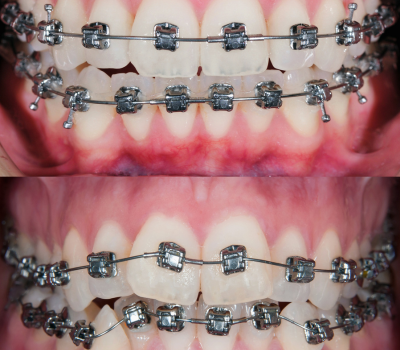

Orthodontic treatment helps correct misaligned teeth and bite issues, improving both function and appearance. With options like braces and clear aligners, you can achieve a straighter, healthier smile.

No two smiles are the same, which is why we provide a variety of orthodontic solutions to fit different lifestyles and dental needs.